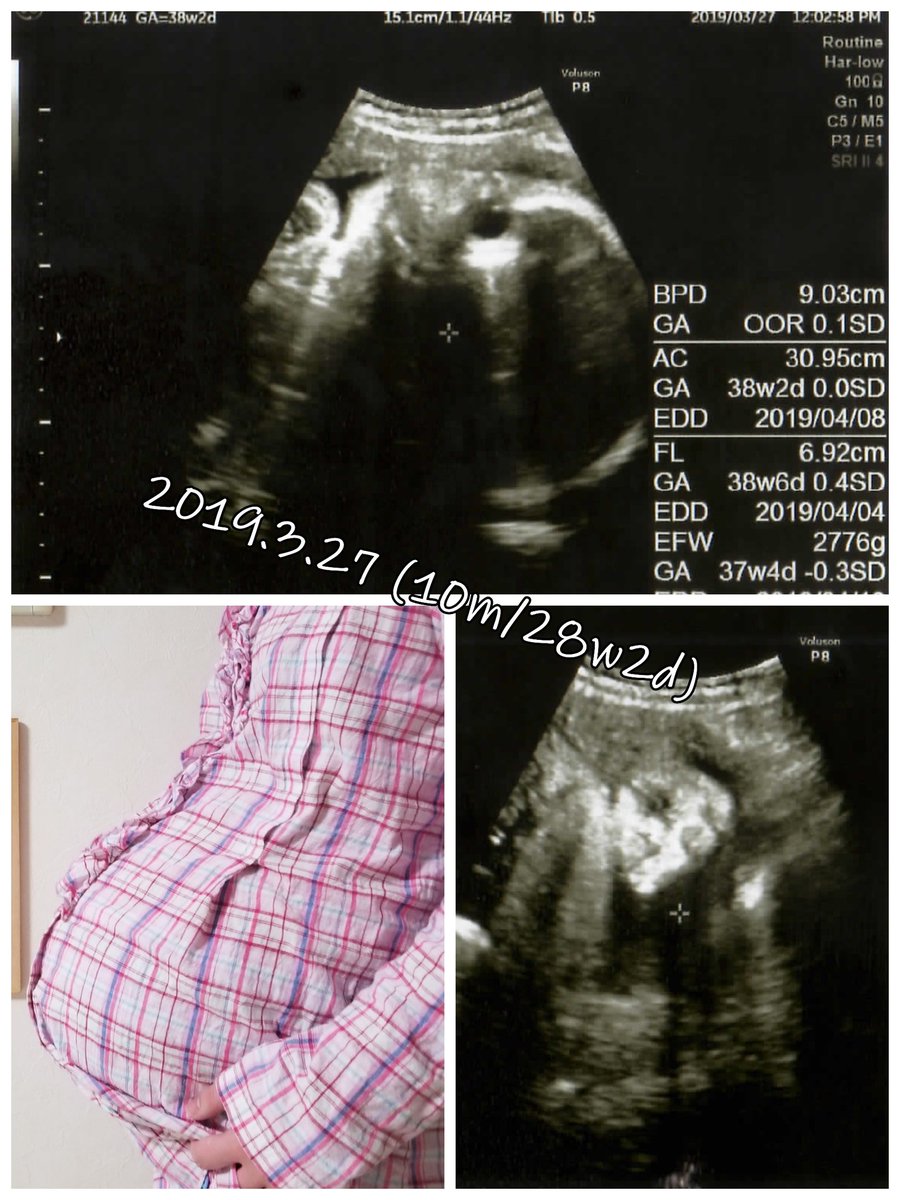

2019.3.27 もう赤ちゃん待ち状態…! お腹もパンッパンです。 エコー載せます、閲覧注意! #育児漫画 #育児日記 #妊娠 #臨月 #妊娠10ヶ月 #正期産 #妊婦健診 #ママ垢さんと繋がりたい #オリジナル漫画 #絵描きさんと繫がりたい pic.twitter.com/RiBXFKKEiP

2019-09-07 10:11:40 拡大

拡大

拡大

拡大